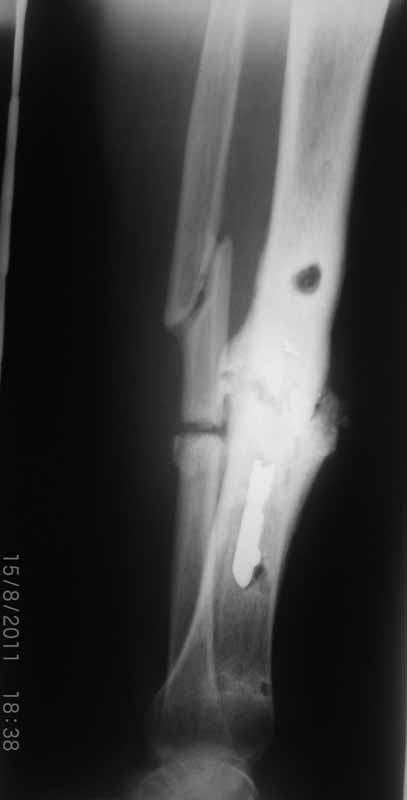

Спасибо за сообщения! Но мне видится что концы отломков большеберцовой кости мертвые. И поэтому мне представляется сомнительным что на гвозде даже с обработкой зоны ложного сустава и костной пластикой что-нибудь срастется. Может я и не прав, но по моему без резекции концов сантиметра на 4 перелом не срастется. Но, опять же, жду советов.

Мне кажется, в первую очередь надо заниматься спицевым остеомиелитом! Надо посмотреть фото голени.

С уважением Абдурашид.